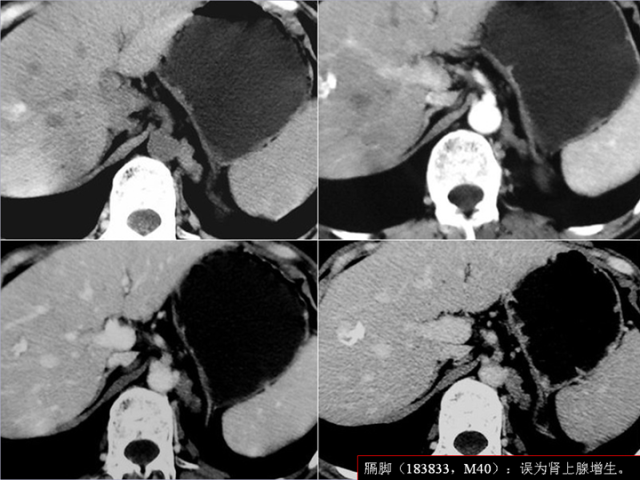

膈肌角解剖及常见变异

作者:王俭 上海长征医院